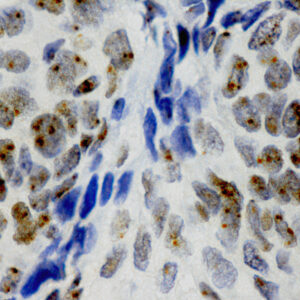

BioGenex offers fluorescein-labeled oligonucleotide probes to detect DNA or RNA using In situ Hybridization (ISH). These probes allow quantitative detection of specific DNA/RNA sequences in their native form within the cells of formalin-fixed paraffin-embedded (FFPE) tissue sections. These probes offer reliable, highly sensitive, and easy-to-perform DNA and RNA ISH assays when used with the BioGenex ISH Detection Systems.